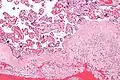

Micrograph of a chronic deciduitis, showing the characteristic plasma cells. H&E stain.

Chronic deciduitis is a type of long-lasting inflammation that arises in pregnancy and affects the endometrial stromal tissue (decidua).

It is associated with preterm labour.[1] The diagnosis rests primarily on the presence of plasma cells.[2]